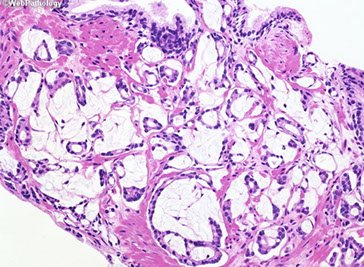

Clear Cell Cribriform Hyperplasia

Occurs in transition zone, mostly in TURP for urinary obstructive sx and rarely needle bx

- some consider it a cribriform variant of BPH

- made of numerous cribriform glands separated from each other by modest amt of stroma in pattern of nodular hyperplasia

- if florid, can infiltrate stroma diffusely and have back-to-back glands

- if misdiagnosed, would be Gleason 4+4=8

Micro: epithelial cells have clear cytoplasm and small bland nuclei c inconspicuous or small nucleoli

- around man of the glands is a strikingly prominent basal cell layer c row of cuboidal darkly stained cells beneath the clear cells

- basal cells may form small knots at the periphery of some of the glands

- basal cells can occasionally have small nucleoli

- basal layer may also be inconspicuous or incomplete

- although usually unnecessary, HMWK stains basal cells

Distinguishing bwt clear cell cribriform hyperplasia and cribriform PIN can be difficult

- easier to diff from ca, which doesn't have basal cells

- clear cell cribriform hyperplasia probably unrelated to AC